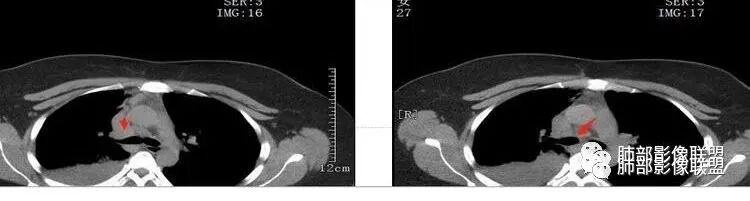

关键点——中间段支气管堵塞处

通过视频显示中间段堵了

支气管腔内占位

远端低强化,提示粘液很多

本病例特点是中叶病灶和下叶病灶不一样,支气管腔内的病灶又是怎么样的呢?我们要是有沿支气管重建的冠状位、矢状位会更有利于分析。第一,中叶病灶明显粘液样改变、低密度,且低密度区有占位效应、膨隆,确实要考虑粘液表皮样癌。第二,中叶和下叶支气管显示不出来,但血管显示出来了。中叶病灶血管稀疏、细小,下叶病灶血管粗大、走形正常。朝外肺不张实变,不是单纯的肺不张,肺不张一般体积明显缩小、血管聚拢,该病例肿瘤于其中成分不一样,所以上叶部分病灶考虑为下叶病灶占位效应及膈面向上推压引起,中叶萎缩。综合腔内堵塞、纵隔淋巴结肿大要考虑恶性。

3.中间段支气管阻塞,腔内隐约见息肉样结节或突入,结节有较明显强化,这很重要,说明它有生命力,强烈提示新生物,而非分泌物或异物等等。

可惜腔内腔外混沌一片,我们不能分辨管壁及管壁外细节,我们不能判断新生物实际大小,不能判断局部支气管彻底破坏还是结节影跨越腔内外。

4.年轻、女性,支气管腔内相关新生物,会想到类癌或涎腺类肿瘤,如粘液表皮样癌等。强化较明显类癌可能性较大。支气管鳞癌和间叶组织肿瘤的可能性都非常小。